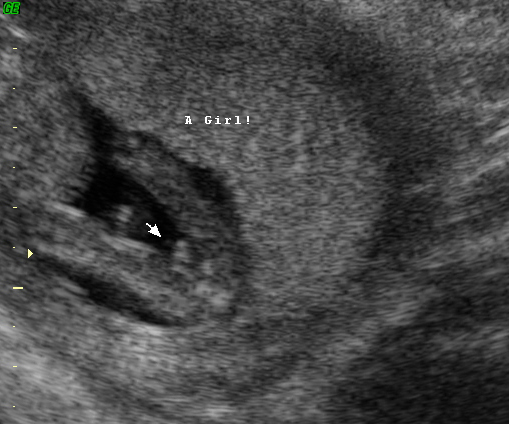

Confirmed girl :) Nub shot at 12.5w, potty at 14, potty at 16 and confirmed at 20w

Nubs:

I think probably around 95ish% said girly nubs: